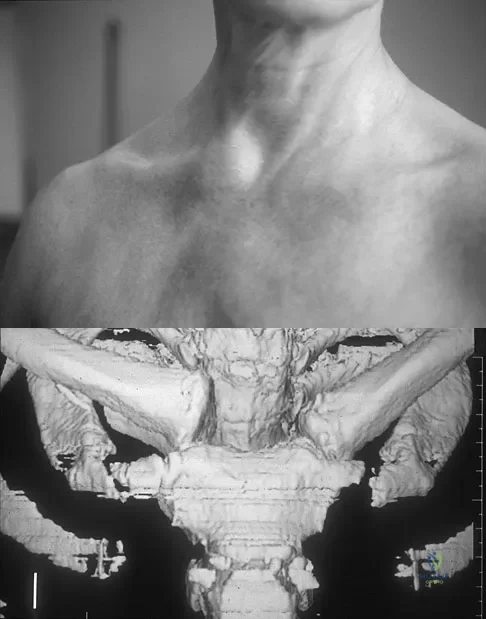

Figure 11a shows the clinical photograph of a 46-year old woman who reports a 3-week history of pain and a "lump" at the base of her neck. She is otherwise in good health and denies any trauma. A 3-D reconstruction CT is shown in Figure 11b. What is the most likely diagnosis?

Explanation